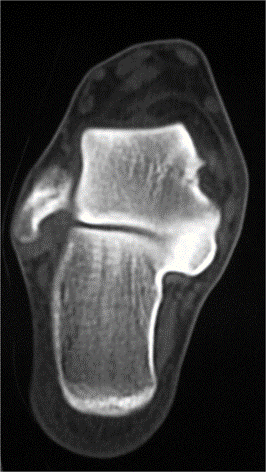

Fig. 2 La TC ha dimostrato la coalizione talo-calcaneare della sfaccettatura subtalare media.